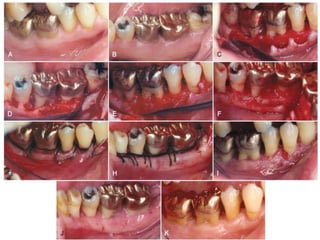

DISTAL MOLAR SURGERY

▸ The treatment of periodontal pockets on the distal

surface of terminal molars is often complicated by

the presence of bulbous fibrous tissue over the

maxillary tuberosity or prominent retromolar pads

in the mandible

▸ Deep vertical defects are also often present in

conjunction with the redundant fibrous tissue

▸ Some of these osseous lesions may result from

incomplete repair after the extraction of impacted

third molars

▸ The gingivectomy incision is the most direct

approach to the treatment of distal pockets that

have adequate attached gingiva and no osseous

lesions

▸ However, the flap approach is less traumatic

postsurgically because it produces a primary

closure wound rather than the open secondary

wound left by a gingivectomy incision

▸ Maxillary Molars

▸ The treatment of distal pockets on the maxillary

arch is usually simpler than the treatment of a

similar lesion on the mandibular arch, because the

tuberosity presents a greater amount of fibrous

attached gingiva than does the area of the

retromolar pad

▸ In addition, the anatomy of the tuberosity that

extends distally is more adaptable to pocket

elimination than is that of the mandibular molar

arch, where the tissue extends coronally

▸ However, the lack of a broad area of attached

gingiva and the abruptly ascending tuberosity

sometimes complicate therapy

▸ Technique: Two parallel incisions that begin at the

distal portion of the tooth and extend to the

mucogingival junction distal to the tuberosity or

retromolar pad are made

▸ The faciolingual distance between these two

incisions depends on the depth of the pocket and

the amount of fibrous tissue involved

▸ The deeper the pocket, the greater is the distance

between the two parallel incisions

▸ A transversal incision is made at the distal end of the

two parallel incisions so that a long, rectangular piece

of tissue can be removed

▸ The parallel distal incisions should be confined to the

attached gingiva, because bleeding and flap

management become problems when the incision is

extended into the alveolar mucosa

▸ If access is difficult especially if the distance from the

distal aspect of the tooth to the mucogingival junction

is short then a vertical incision can be made at the end

of the parallel incisions

▸ When treating the tuberosity area, the two distal

incisions are usually made at the midline of the

tuberosity

▸ These incisions are made straight down into the

underlying bone, where access is difficult. A no. 12B

blade is generally used.

▸ Mandibular Molars

▸ The retromolar pad area does not usually present as

much fibrous attached gingiva. The keratinized

gingiva, if present, may not be found directly distal to

the molar

▸ The greatest amount may be distolingual or

distofacial, and it may not be over the bony crest

▸ The ascending ramus of the mandible may also create

a short, horizontal area distal to the terminal molar

▸ The shorter this area, the more difficult it is to treat any

deep distal lesion around the terminal molar

▸ The two incisions distal to the molar should follow the

area with the greatest amount of attached gingiva

▸ Therefore, the incisions could be directed

distolingually or distofacially, depending on which

area has more attached gingiva